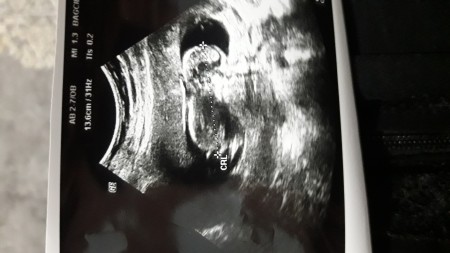

Hamilelik Dönemi Genel kategorisinde (17 puan)

kızlar resimden cinsiyet tahmini yapan ve tutturan varmi banada yazsın...

Kapatılma nedeni: Cinsiyet tahminlerini sol üst köşeden sohbet bölümünden sorabilirsiniz anlayışınız için teşekkürler

Ben içime doğanı sölüyorum hep erkek <3